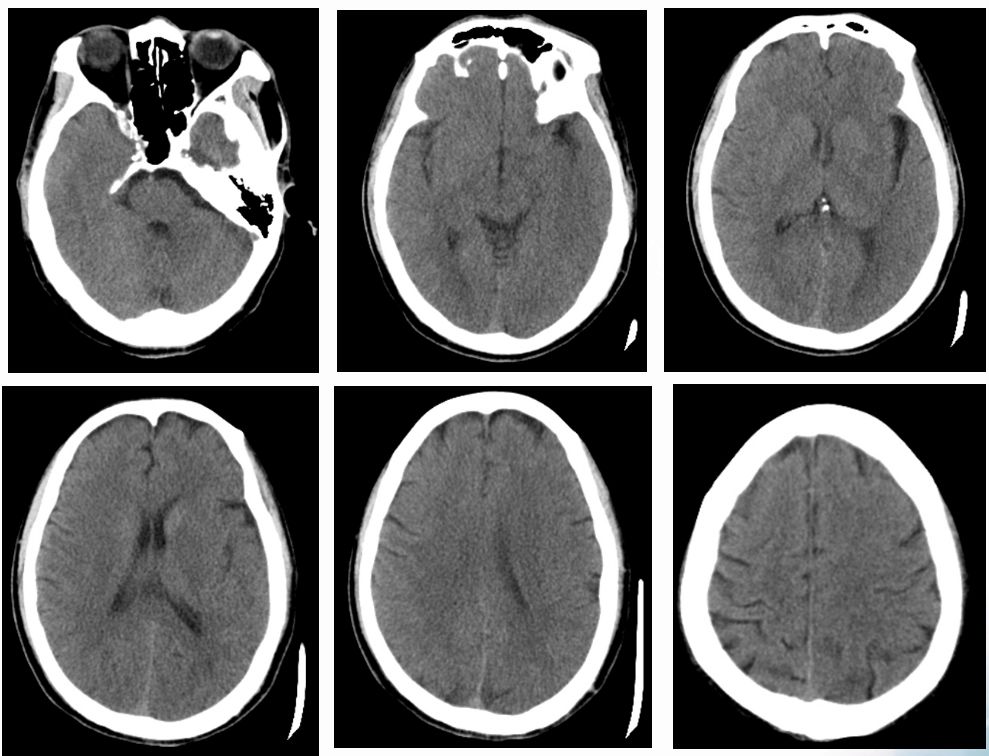

术前CT

ASPECTS评分 8分

术后即刻CT

术后24h CT

术前NIHSS评分16分

术后24hNIHSS评分 2分

术后48hNIHSS评分

术后第3天,患者突然意识丧失,呼叫无反应,刺激右侧肢体无反应,左侧可见回缩,紧急头颅CT提示左侧半球大量脑出血并破入脑室,很快左侧瞳孔散大,深昏迷,家属拒绝行开颅血肿清除术,自动出院。

术后3天CT: